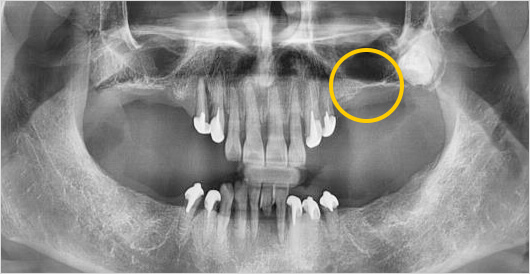

고난이도 임플란트 (상악동 거상술) 수술 전

고난이도 임플란트 (상악동 거상술) 수술 후